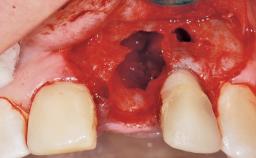

Immediate Flapless Placement of an Implant in a Maxillary Right Lateral Incisor Site

This 43-year-old male patient, a non-smoker, came to our practice because of a fracture of tooth 12 caused by a bicycle accident. Due to the combined para- and infrabony crown and root fracture, tooth extraction, and subsequent implant placement were suggested to the patient as the therapy of choice. The patient had high esthetic expectations with regard to the treatment outcome and asked for an immediate fixed provisional restoration. His individual esthetic risk profile summed up to a medium esthetic risk.

| Soft Tissue Anatomy | Intact | Defective | |

| Socket Integrity | Sufficient, with intact bone walls |

| Bone Volume | Sufficient, with intact walls |